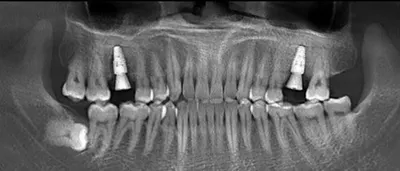

江小姐因為下牙前牙區缺牙,講話時洞口明顯,前一陣子參加國中同學會被老同學笑,除了下牙區缺牙之外,上牙區的牙齒也卡了許多汙垢,甚至有蛀牙發黑的情形,同學發現後開始針對牙齒議題展開熱烈討論,大家一直勸江小姐要趕快治療,因為缺牙這種問題久了會連帶導致周圍牙齒越壞越多顆。後來同學介紹她到禾睿牙醫....